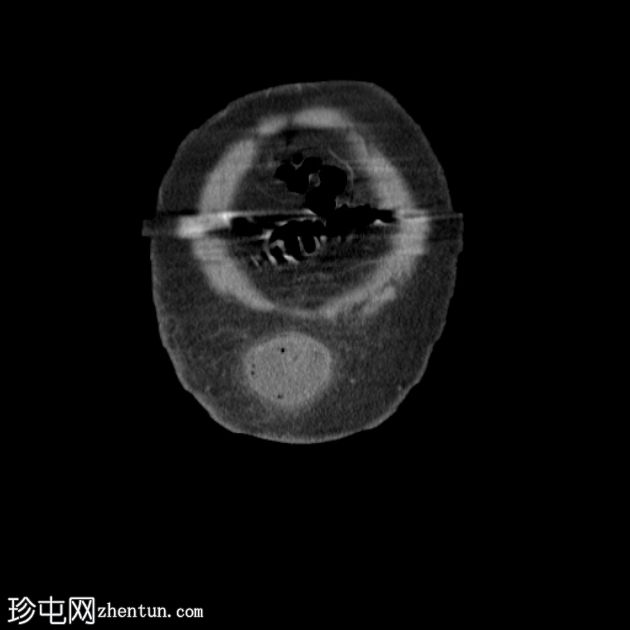

冠状位

平扫

多处扩张的小肠袢内可见多个气液平面,直至进入脐疝的肠袢处可见移行点,而从疝口出来的远端小肠袢则呈塌陷状态。

诊断:嵌顿性脐疝继发急性小肠梗阻。